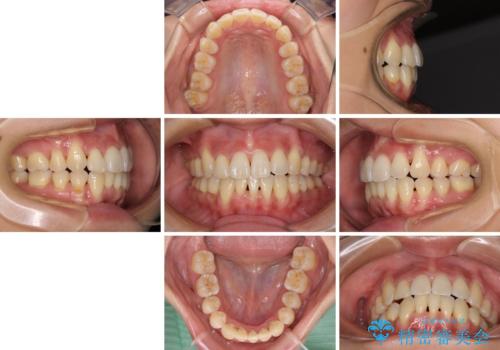

通常であれば、上下顎左右小臼歯各1歯の合計4本を抜歯しますが、歯肉退縮の著しい下顎前歯を抜歯して欲しいという患者様の強い希望により、上顎のみ左右小臼歯2歯を、下顎は前歯を1歯を抜歯することとしました。

抜歯する歯を変更したため奥歯の咬合はアンバランスとなりましたが、前歯は綺麗に整い、歯肉退縮も回避できました。